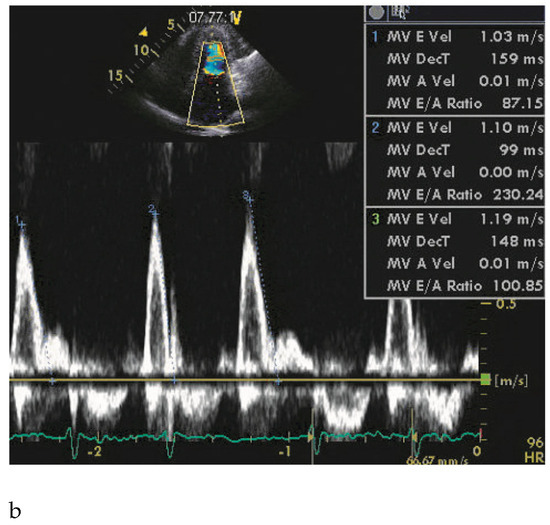

Hypertrophic Nonobstructive Cardiomyopathy as a Cause of Severe Restrictive Physiology

by Stéphane Noble, Caroline Frangos and Philippe L’Allier

66-year-old woman with a family history of hypertrophic cardiomyopathy (HCM) presented with severeprogressive exertional dyspnoea. She had recently complained of palpitations corresponding to atrial fibrillation on the ECG […] Full article

Figure 1